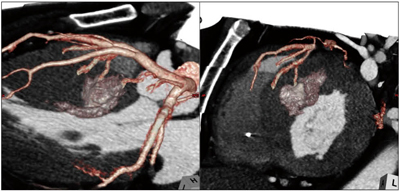

図3は、対角枝から分岐する中隔枝が冠動脈CT画像で確認された症例であり、第一中隔枝からの分枝を含めて2本の枝がCT画像上での焼灼対象と考えられた。コントラストエコーでも、同2枝に関しては左室流出路の心筋内膜側を灌流していることが確認されたが、第一中隔枝の本幹は右室側を灌流しており、焼灼対象ではなかった(図4)。術直後に施行された冠動脈CT検査では、エタノール動注された2枝の末梢側を中心に焼灼心筋部位が遅延造影されており、コントラストエコーでの灌流域と一致していた(図5)。このような症例を経験し、われわれは、より正確に焼灼対象となる中隔枝を選択するには冠動脈CT画像の活用が有効であると考えている。

図5 PTSMA直後に施行された冠動脈CT画像

2枝の中隔枝末梢側で焼灼心筋が遅延造影されており、焼灼部位の確認ができる。